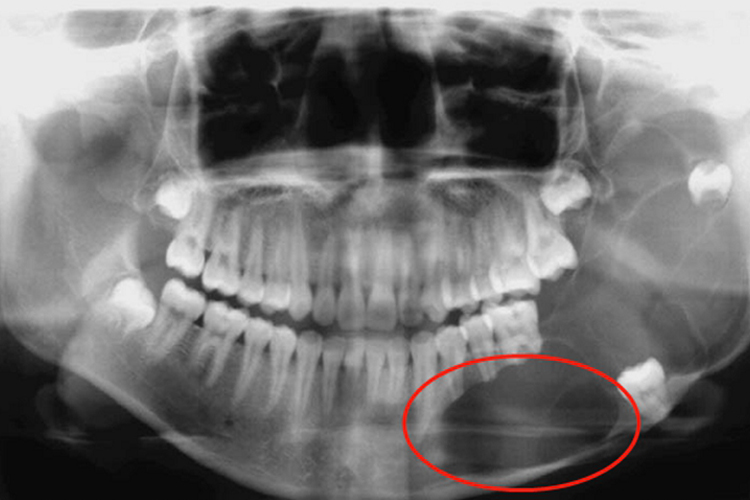

X线表现为颌骨内囊状低密度灶,多向颊侧膨胀性生长,边缘骨质硬化,有多发切迹;病灶内可能含有牙齿,骨皮质受压变薄甚至吸收。CT表现为低密度灶,周围囊壁境界清晰,呈锐利高密度影。